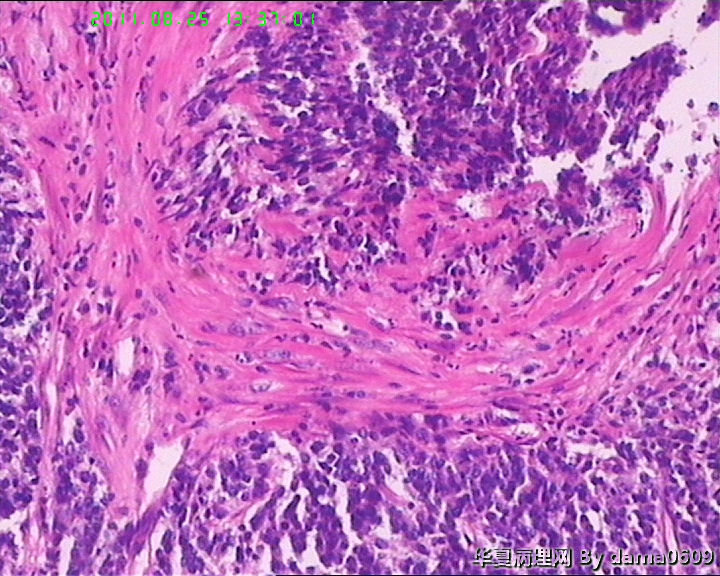

患者男性,39岁。以回盲部肿物行肠镜检查、活检。镜下四块组织内有两块见呈巢状的小细胞(如图

),另两块为粘膜慢性炎表现及坏死组织。学生不知如何分类:未分化癌?类癌?小细胞癌?请老师指教。谢谢!

细胞核较小、深染、一致,核分裂象少见,支持典型类癌。

神经内分泌肿瘤 淋巴瘤 低分化腺癌。。。

楼主是想说“未分化癌”?片子切的比较厚,考虑神经内分泌肿瘤,低分化腺癌待排。